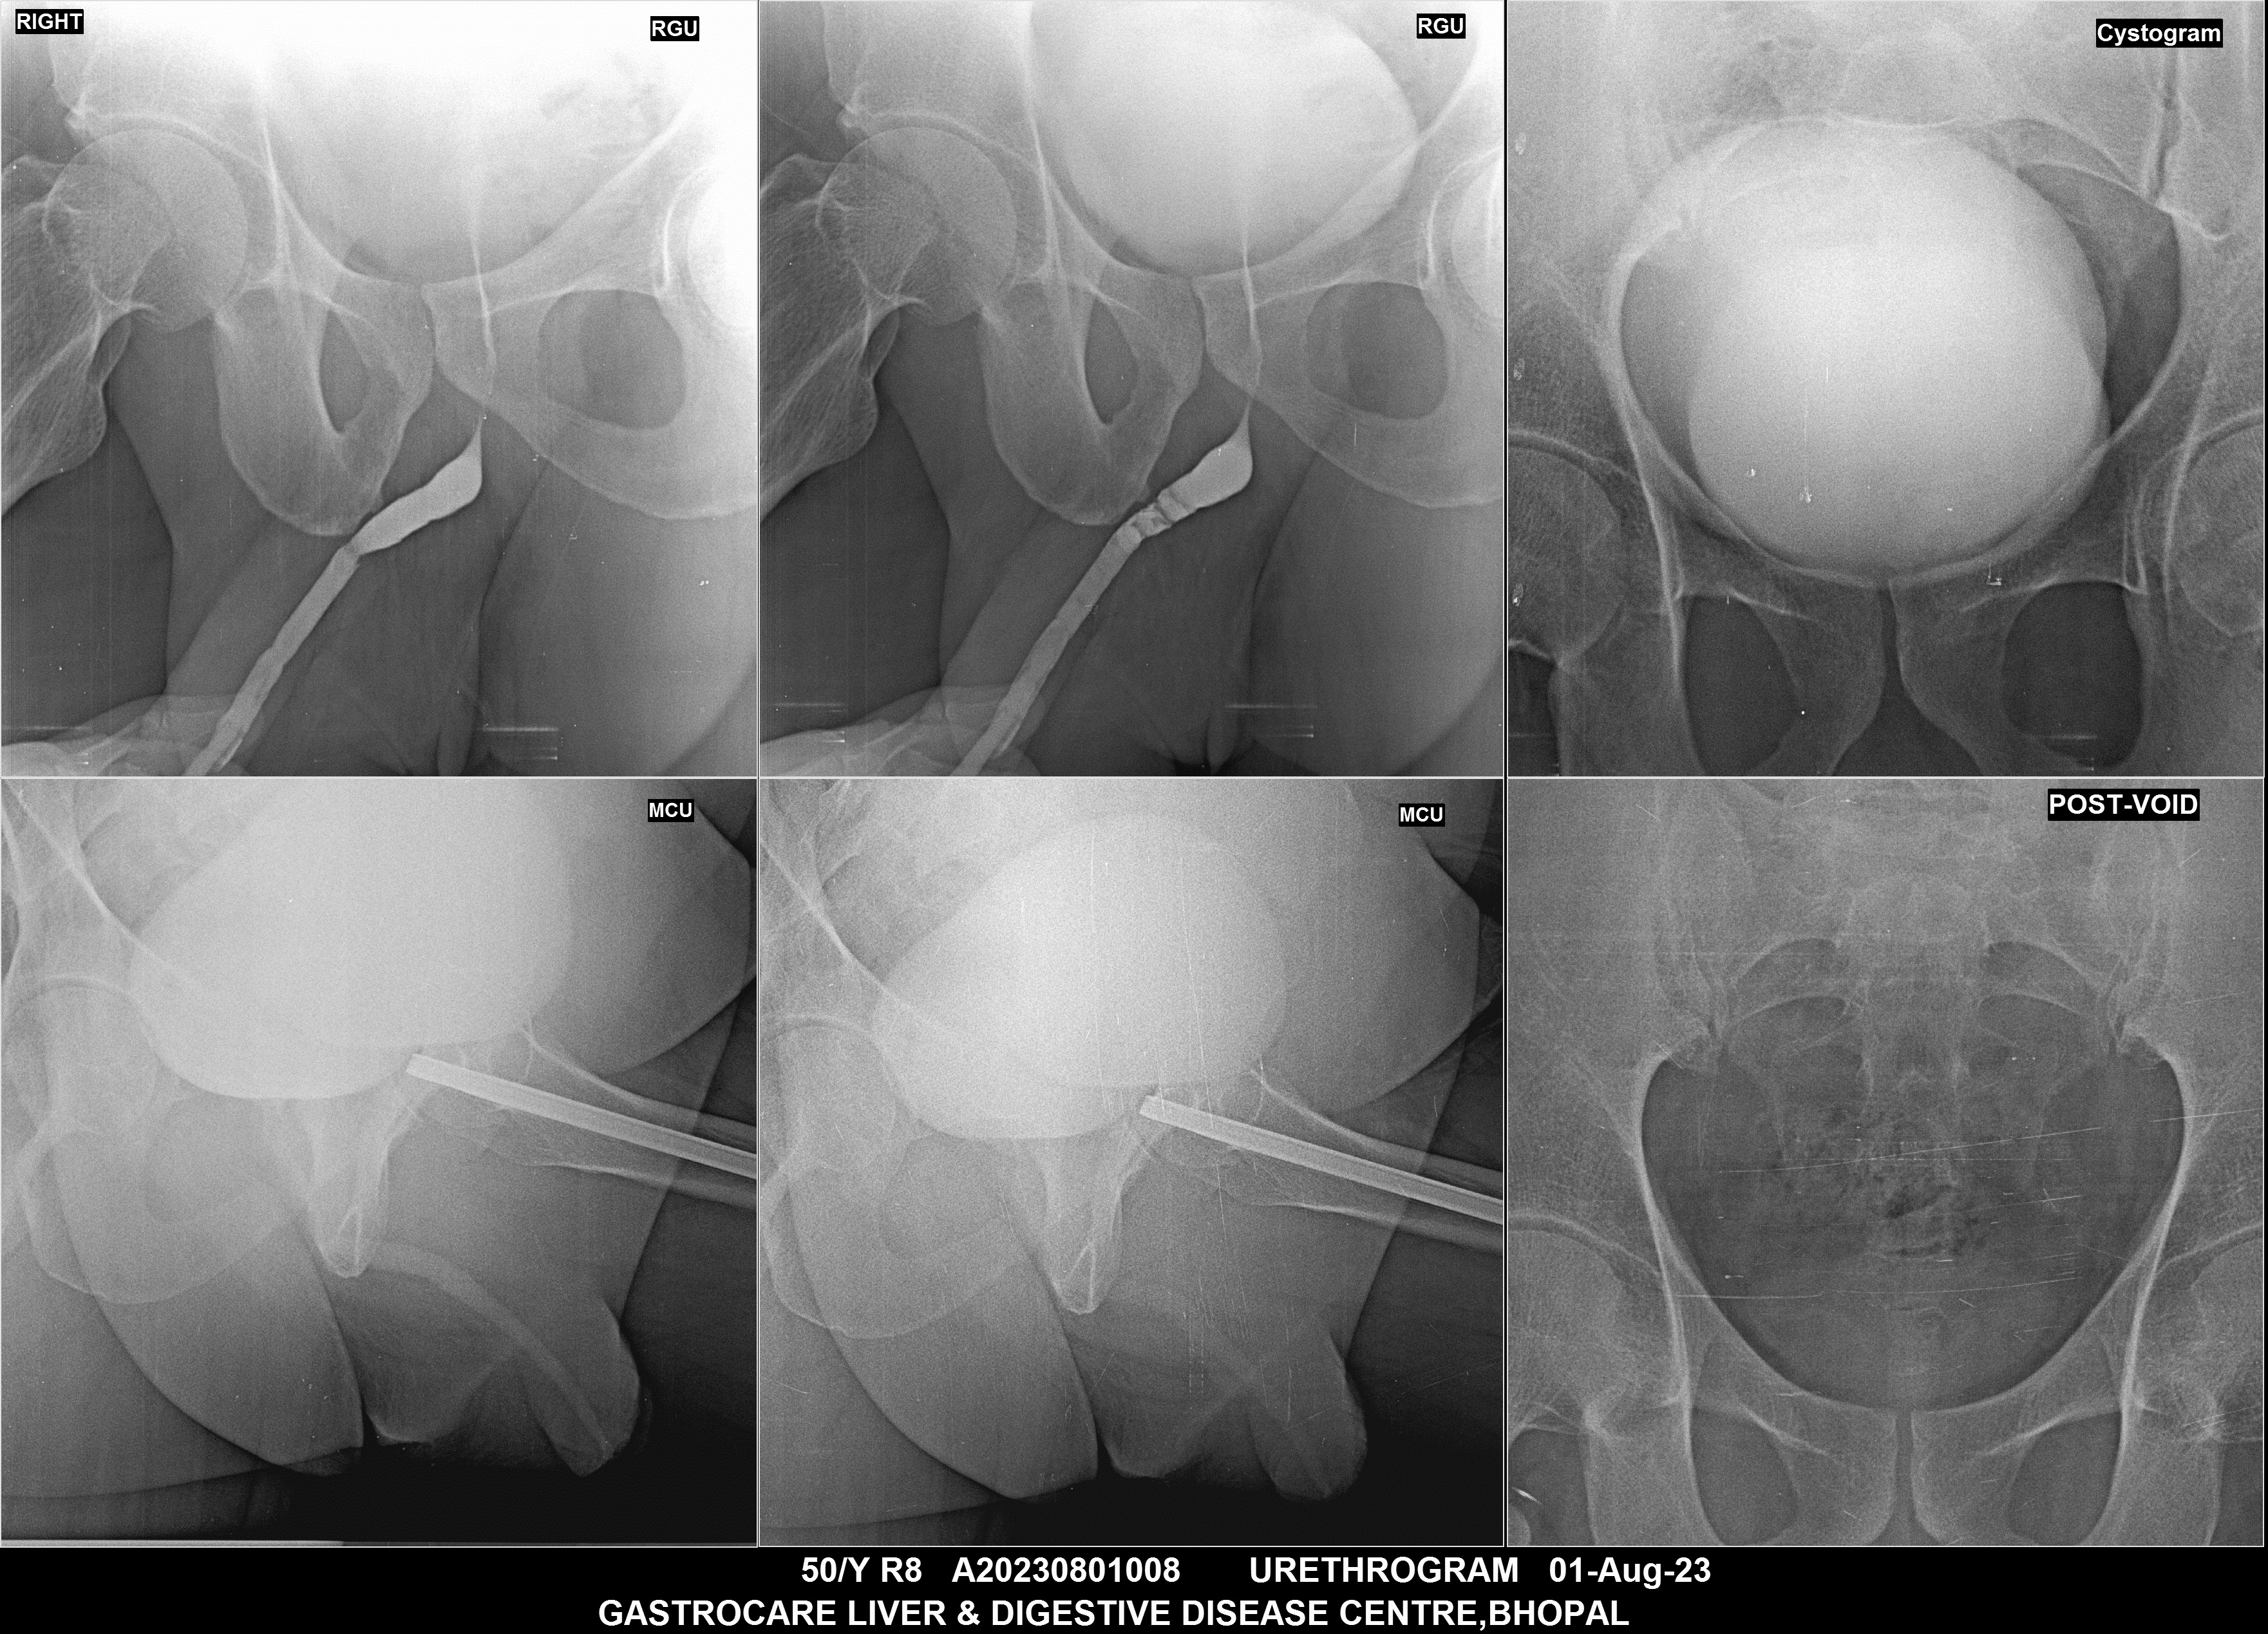

Section: URETHROGRAM Total: 95 images